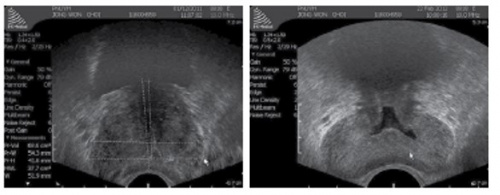

• 전립선 크기 측정

TRUS의 가장 큰 목적 중에 하나는 전립선의 크기를 측정하는 것이다. Transverse view에서 너비(width)와 높이(height)를 측정하고 sagittal view에서 길이(length; bladder neck ~ apex)를 측정한 후 편장형타원체공식(ellipsoid volume formula)을 이용하여 계산한다.

전립선 용적 = Ω/6 x H x W x L (Ω/6 ≈ 0.523)

대부분의 초음파 기계는 이 공식을 자동으로 계산해 준다.